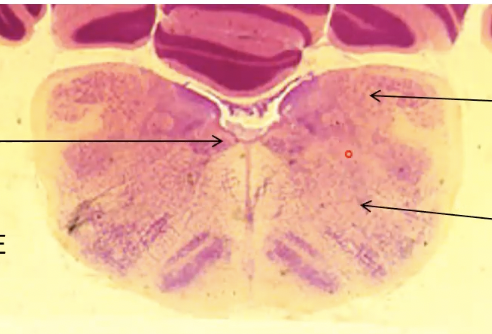

3

Q